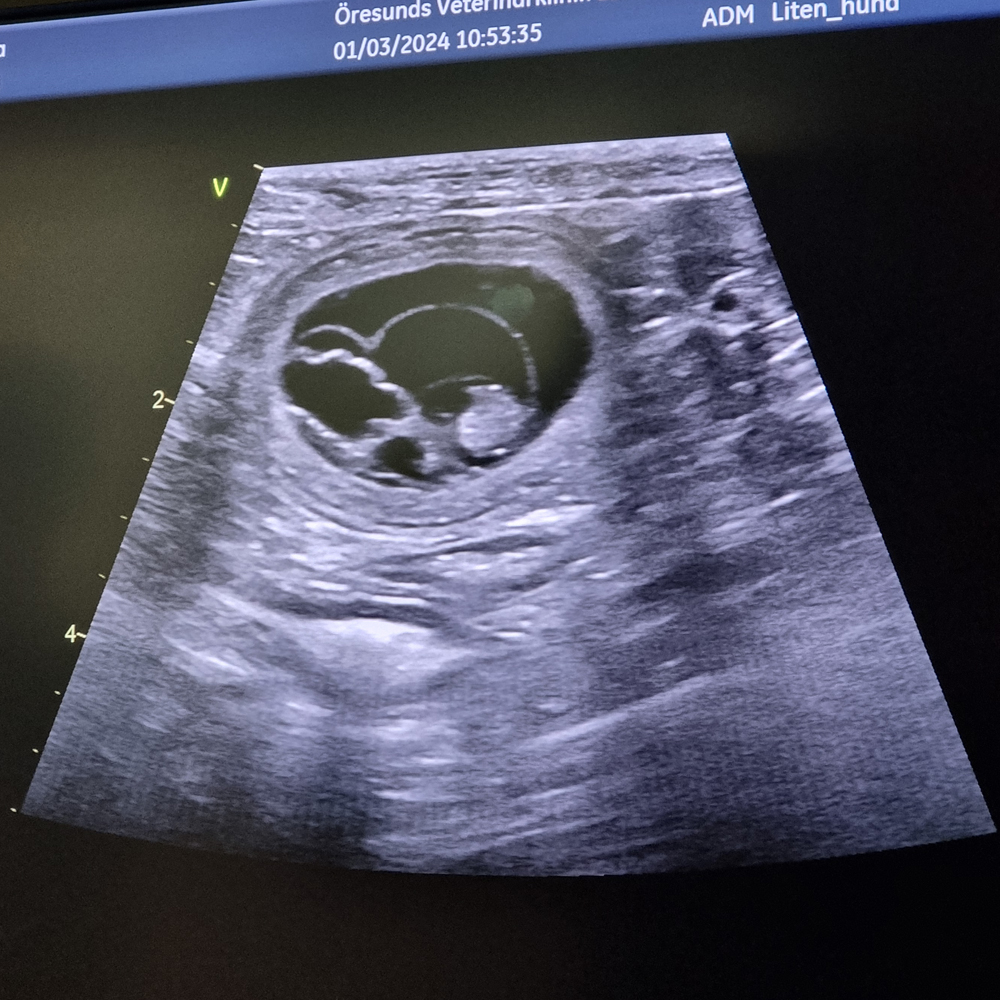

Idag har vi gjort ett ultraljud på Märta för att se om hon är dräktig... och det var hon!

Det blir ingen stor kull men väl så efterlängtad.

Bilden är från ultraljudet där det syns ett par fosterblåsor.